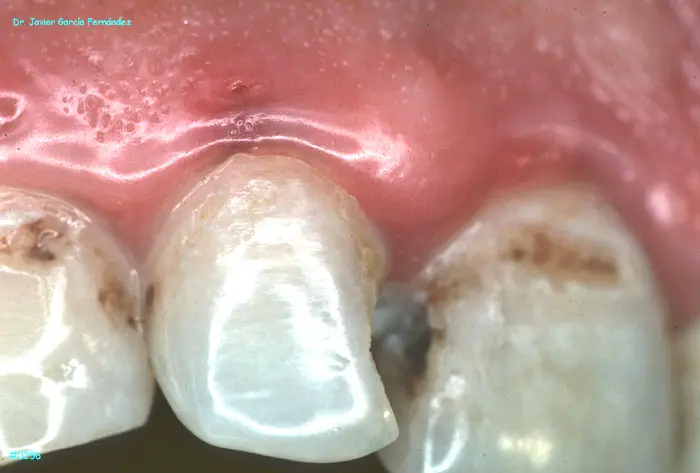

ATLAS DE CIRUGIA PERIODONTAL